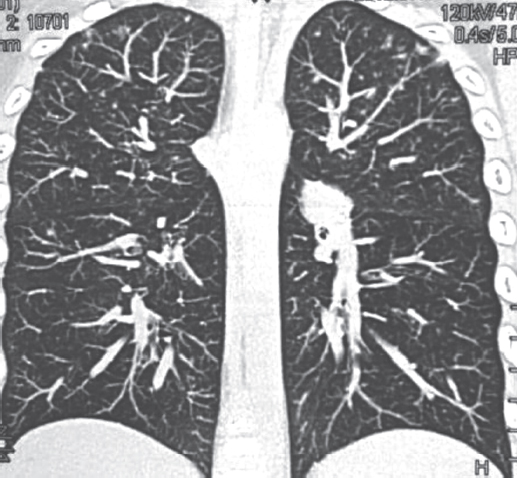

С 07.06.2012 начато лечение ОЛЛ по программе ALL–MB-2008. Ребенок получал дексаметазон, винкристин, рубомицин на фоне массивной антибактериальной терапии (меропенем, амикацин, флуконазол). Отмечались осложнения: нейтропения, токсическое поражение печени, почек, полинейропатия, язвенно-эрозивное поражение пищевода с положительной динамикой на фоне проводимой терапии. Ремиссия достигнута к 36-му дню терапии ОЛЛ (12.07.2012). Миелограмма на 36-й день терапии. 12.07.12: ядерность костного мозга 40,0 · 109/л, бласты — 0,4 %. Проведены курсы консолидации 1, 2, 3. Состояние ребенка улучшилось, контрольное МСКТ-исследование легких 27.06.2012 выявило положительную динамику рассасывания инфильтративных изменений в легочной ткани, плеврального выпота. Однако в связи с появлением хрипов в легких 19.07.2012 выполнена контрольная МСКТ грудной клетки, на которой обнаружено появление множественных двусторонних очагов в легких (рис. 3).

Рис. 3. Пациент, 6 лет. Компьютерная томография грудной клетки 19.07.2012: появление множественных двусторонних очагов в верхних отделах легких

Fig. 3. Patient, 6 years old. Chest computed tomography 19.06.2012: the appearance of multiple bilateral foci in the upper lungs

20.07.12 проведена фибробронхоскопия со взятием бронхоальвеолярного лаважа (БАЛ). Исследование БАЛ на МБТ: полимеразная цепная реакция двукратно, микроскопия и посев отрицательны. Микроскопия и посев БАЛ на грибы выявили Aspergilla niger, диагностирован инвазивный аспергиллез. Проведен курс терапии противогрибковым препаратом вориконазолом с положительной динамикой клинической и лабораторной. МСКТ: контрольное обследование 21.08.2012 — без патологических изменений в легких. Всего на отделении гематологии ДГБ № 1 ребенок находился с 31.05.2012 по 06.02.2013 (с перерывами). Весь этот период мальчик наблюдался фтизиатром, получал противотуберкулезную терапию: изониазид (с 08.06.2012 по 25.10.2012), пиразинамид (с 08.06.2012 через день по 25.10.2012), этамбутол (08.06.2012–23.07.2012 через день), ПАСК (24.07.2012–28.10.2012). 25.10.2012 установлено клиническое излечение туберкулеза, перевод в группу III-Б диспансерного учета.